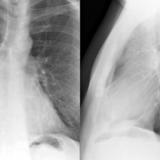

Part'l abs peric Lat

Date: 07/23/2006

Views: 3194